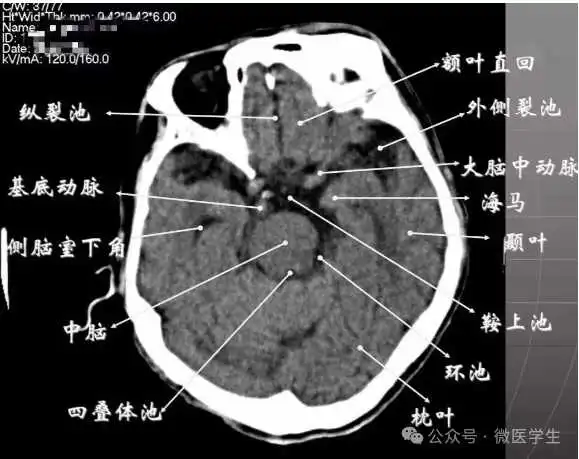

- 鞍上池:在垂体窝上方,位于两侧颅中窝之间,前界为颞叶直回,侧方位颞叶海马,呈五角星形或六角星形。其前角连于纵裂池,两外侧角连于外侧裂池,两后外侧角延续于环池,第六个角位于后缘中间,是角间池。鞍上池边缘为大脑动脉环,池内前部常可见“v”字型视交叉。

- 颅后窝:四脑室或四叠体池。

显示侧脑室前角的下部:

- 前方---额叶;外侧---尾状核头部;后方中线处---第三脑室,其两侧连接丘脑。